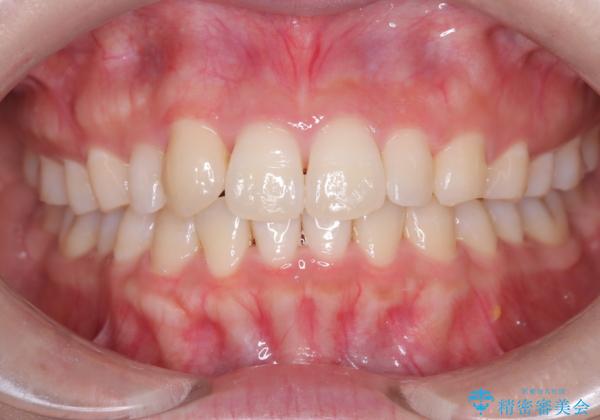

【インビザライン】八重歯が気になる

- 乳歯を抜歯してスペースを確保し八重歯の改善を行いました。

インビザラインをしっかり使用していただいたので、きれいな歯並びになりました。